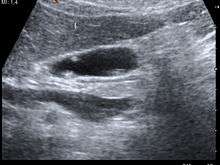

| A polyp in the gall bladder as seen on ultrasound | |

Gallbladder polyps are growths or lesions resembling growths (polypoid lesions) in the wall of the gallbladder. True polyps are abnormal accumulations of mucous membrane tissue that would normally be shed by the body. The main types of polypoid growths of the gallbladder include cholesterol polyp/cholesterosis, cholesterosis with fibrous dysplasia of gallbladder, adenomyomatosis, hyperplastic cholecystosis, and adenocarcinoma.

Diagnosis is typically by ultrasound or CT imaging.